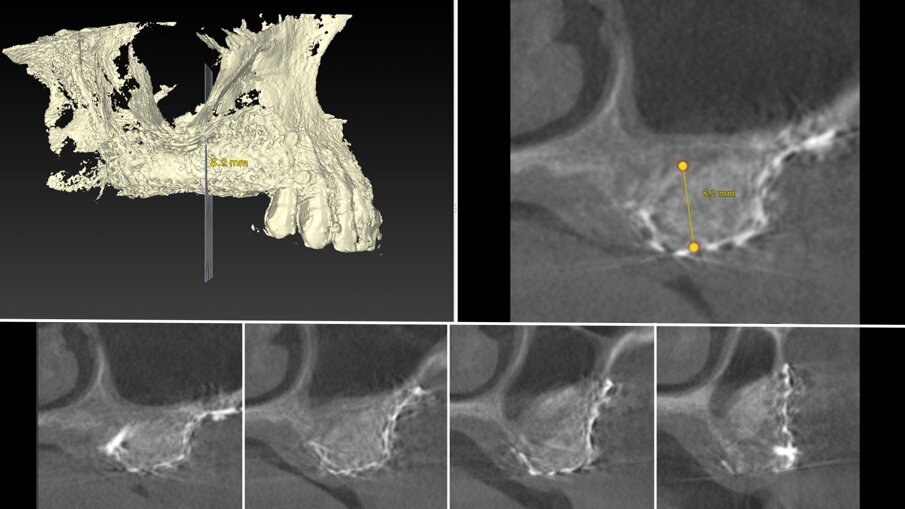

Una paziente di 62 anni, ASA I, non fumatrice e non diabetica, con malattia parodontale precedentemente trattata, si è presentata per una riabilitazione implanto-protesica del mascellare superiore (Fig. 1). L’analisi radiografica, eseguita tramite ortopantomografia (OPT) e tomografia computerizzata cone-beam (CBCT), ha rilevato la presenza di un difetto osseo verticale nel primo sestante, dovuto alla completa perdita del processo alveolare (Figg. 2, 3). Dopo aver discusso con la paziente le possibilità di trattamento, è stato accettato il trattamento proposto come prima scelta, ovvero la ricostruzione ossea del processo alveolare e la successiva riabilitazione mediante corone singole su impianti.

Il piano di trattamento è stato sviluppato utilizzando un flusso di lavoro completamente digitale. Pertanto, i files .DICOM ottenuti dalla CBCT pre-operatoria sono stati utilizzati per generare una ricostruzione 3D del mascellare, che ha permesso di eseguire la progettazione virtuale del volume osseo “ideale” per l’inserimento di 3 impianti in sede #15, #16, e #17. (Figg. 4, 5). Successivamente, è stata creata virtualmente la griglia customizzata corrispondente al volume aumentato nel mascellare della paziente (Fig. 6). Il giorno della chirurgia ricostruttiva (T0), è stata eseguita una profilassi antibiotica (2 g di amoxicillina con acido clavulanico e 500 mg di metronidazolo), una profilassi antinfiammatoria (20 mg di piroxicam), una sedazione cosciente x os (2 ml di delorazepam e 2 ml di diazepam), e disinfezione del cavo orale (risciacquo orale con povidone-iodio per un minuto, perossido di idrogeno per due minuti, e collutorio alla clorexidina 0,2% per tre minuti), e un’anestesia locale mediante articaina 4% contenente adrenalina 1:100.00018. L’esame obiettivo mostra la gravità del difetto osseo che determina un evidente difetto di volume sia in senso orizzontale che in senso verticale (Figg. 7, 8).